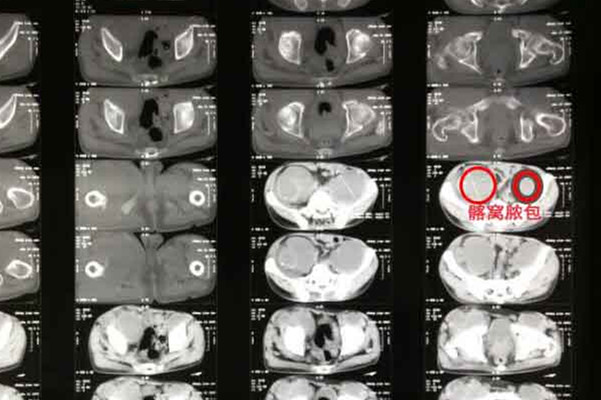

跗骨结核的确诊常需要依靠影像检查和实验室检查。影像检查中X线表现一般在感染结核后 2~5 个月出现,典型的征象即 Phemister 三联征,包括关节周围骨质疏松、骨质破坏和关节间隙逐渐狭窄。Ct检查对骨质的破坏显像良好,能进一步显示早期的骨质破坏及破坏的位置、范围。实验室检查包括行血常规、血沉、C 反应蛋白、穿刺物抗酸染色、培养、活检等。但最终明确诊断还是有待于病理活检,包括穿刺物或病灶清除后的病检,这是诊断骨关节结核的金标准。